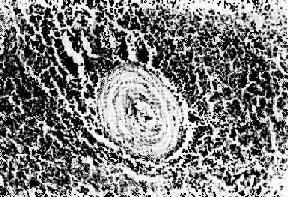

图4-13 结节性多动脉炎 两个动脉壁的各层都有炎性细胞浸润,外膜尤为显著。中膜发生纤维素样坏死 本病病变分布广泛,临床表现变异多端,患者常有低热、乏力、粒细胞增多以及多系统受累的症状,如血尿、肾功能衰竭、高血压、腹痛、腹泻、黑粪及周围神经炎等。病程快慢不一,经免疫抑制治疗,55%患者可存活。 病因与发病机制 病因和发病机制不明,动物实验提示,体液因素在本病的发生中起着重要作用。免疫荧光技术证实,人结节性多动脉炎血管壁中有免疫球蛋白和补体,有些还有HBsAg,约50%患者血清HBsAg或抗HBs阳性。 6.Wegener肉芽肿病 Wegener肉芽肿病是一种少见病,具有以下特点:①小血管急性坏死性脉管炎,可累有各器官的血管,以呼吸道、肾、脾最常受累。表现为小动脉、小静脉管壁的纤维素样坏死,伴弥漫性中性和嗜酸性粒细胞浸润;②呼吸道肉芽肿性坏死性病变,可累及口、鼻腔、鼻旁窦、喉、气管、支气管和肺。病变为由大量积集的单核巨噬细胞、淋巴细胞以及少量多核巨细胞、类上皮细胞、纤维母细胞组成的肉芽肿,中央可陷于成片凝固性坏死。肉眼常形成明显的肿块,表面则因坏死溃破而有溃疡形成;③坏死性肾小球肾炎,表现为在局灶性或弥漫增生性肾小球肾炎的基础上,有节段性毛细血管袢的纤维素样坏死,血栓形成,如未经治疗可发展为快速进行性肾炎,病程凶险,出现进行性肾功能衰竭。 本病的病因不明,由于有明显的血管炎,并于局部可检得免疫球蛋白和补体,提示其发病与Ⅲ型变态反应有关。但呼吸道出现的肉芽肿和坏死性病变,又提示可能与Ⅳ型变态反应有关,临床上应用细胞毒药物大多能使本病缓解。